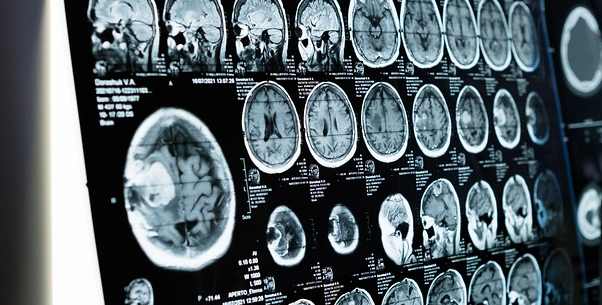

As part of the USC-Caltech MD-PhD Program, Shahrestani began pursuing his Medical Engineering PhD at Caltech in 2018. Upon joining Dr. Tai's lab, he had been new to engineering. However, his neuroscience background gave him the inspiration to reconfigure aerospace circuits for a novel purpose: to find and track anomalies in blood movement in the brain. This application of the technology could provide a rapid and convenient way to keep constant track of stroke progression in patients, an improvement on the current standard of wheeling them through the hospital to get a new MRI scan every hour. Towards the end of 2018 to early 2019, Shahrestani and OTTCP's Licensing Team started the patent process for this technology, which would later become the basis of StrokeDx.

Technology: Noninvasively measuring biological tissues and fluids to generate images of stroke patients